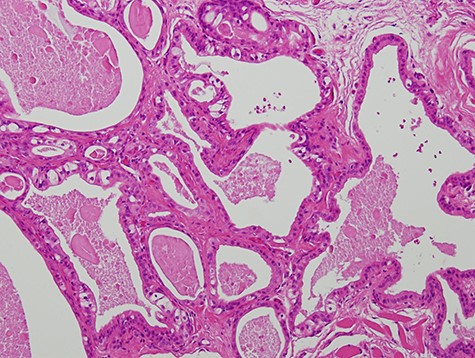

A 63-year-old man was referred to our hospital for treatment of a nodule on his tongue in May 2003. His medical history included Wolff–Parkinson–White syndrome and atrial fibrillation, both of which were controlled adequately by his primary care physician. Physical examination revealed very slight swelling at the right edge of his tongue. The patient reported some spontaneous pain. It was diagnosed as inflammation of the foliate papilla; the patient was followed-up with a gargle prescription. In September 2005, an elastic soft mass, 4 mm in diameter, was observed along the right edge of his tongue (Fig. 1). It was clinically diagnosed as a benign tumour and removed under local anaesthesia. Microscopically, the lesion was composed of multiple cysts of various sizes and shapes, with or without papillary intraluminal short projections (Fig. 2). Many cyst cavities contained eosinophilic fluid. The lesion was well-delineated, but the capsular structure was ill-defined. The stroma was fibrous connective tissue without lymphocytic components. The cystic cavities were lined by a bilayered epithelium composed of luminal columnar cells and basal cuboidal cells. Both luminal and basal epithelial cells were eosinophilic; some clear cells were seen (Fig. 3). Mitotic figures and cellular atypia of epithelial cells were not seen. Immunohistochemically, both luminal and basal cells were CAM5.2+, basal cells were p63+, apical half of the luminal cells were 34βE12+, and the liminal surface was CEA+. The specimen was diagnosed as cystadenoma, based on the histopathological findings.

Micrograph showing the lesion composed of multiple cysts of various sizes and shapes (haematoxylin–eosin stain, 100×).